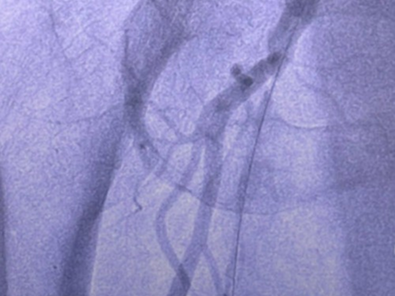

Jetstream : Innovation en Recanalisation Fémorale